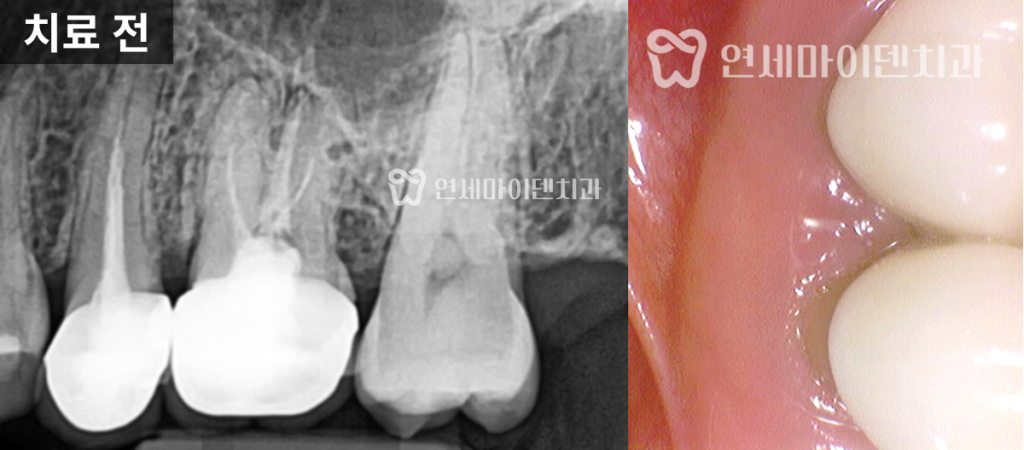

25번 치아 — 재신경치료로 보존

과거 신경치료를 확인해보니,

신경관 충전이 뿌리 끝까지 도달하지 못한 상태였습니다.

충분히 개선 가능성이 있다고 판단하여 재신경치료를 진행했습니다.

내부를 개방해보니, 파란색 레진코어가 들어 있었지만 그 아래에는

IRM, ZOE 등 임시 충전재가 채워져 있었습니다.

이 재료들은 치아와의 접착력이 떨어지기 때문에,

시간이 지나면 틈이 생기고 2차 충치가 발생할 수 있습니다.

결국 이런 부분이 염증의 원인이 된 것입니다.